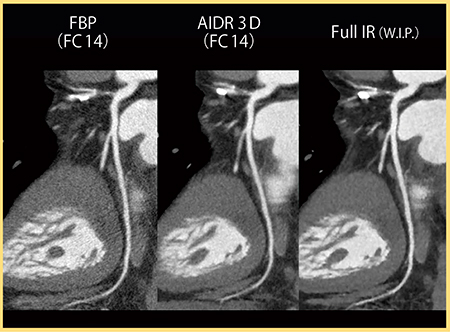

図7は,左前下行枝(LAD)起始部の石灰化症例である。FBPやAIDR 3Dでは,石灰化にブルーミングアーチファクトが見られるが,Full IRではほとんど認められず,石灰化の境界も明瞭である。

図8は,陳旧性心筋梗塞症例の冠動脈CTAであるが,Full IRでは血管や臓器の境界がより明瞭である。心尖部には陳旧性の梗塞巣が認められるが,淡い低吸収の梗塞巣の描出能も向上するのではないかと期待している。図9は同一症例のCurved MPR画像であるが,Full IRではノイズ低減に加え,血管や構造物の境界がきわめて明瞭となっている。

図9 図8のCurved MPR画像